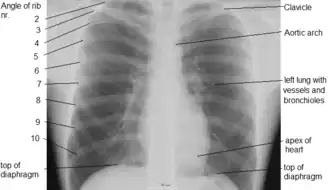

Грудна́я по́лость (лат. cavum thoracis) — анатомическое пространство, ограниченное внутренней поверхностью грудной клетки и верхней поверхностью диафрагмы. Стенки грудной полости выстилает внутригрудная фасция (лат. fascia endothoracica). Центральные отделы грудной полости заняты средостением, по бокам от которого расположены лёгкие. Лёгкие со всех сторон окружены щелевидными плевральными полостями, сформированными висцеральным (внутренним) и париетальным (наружным) листками плевры.